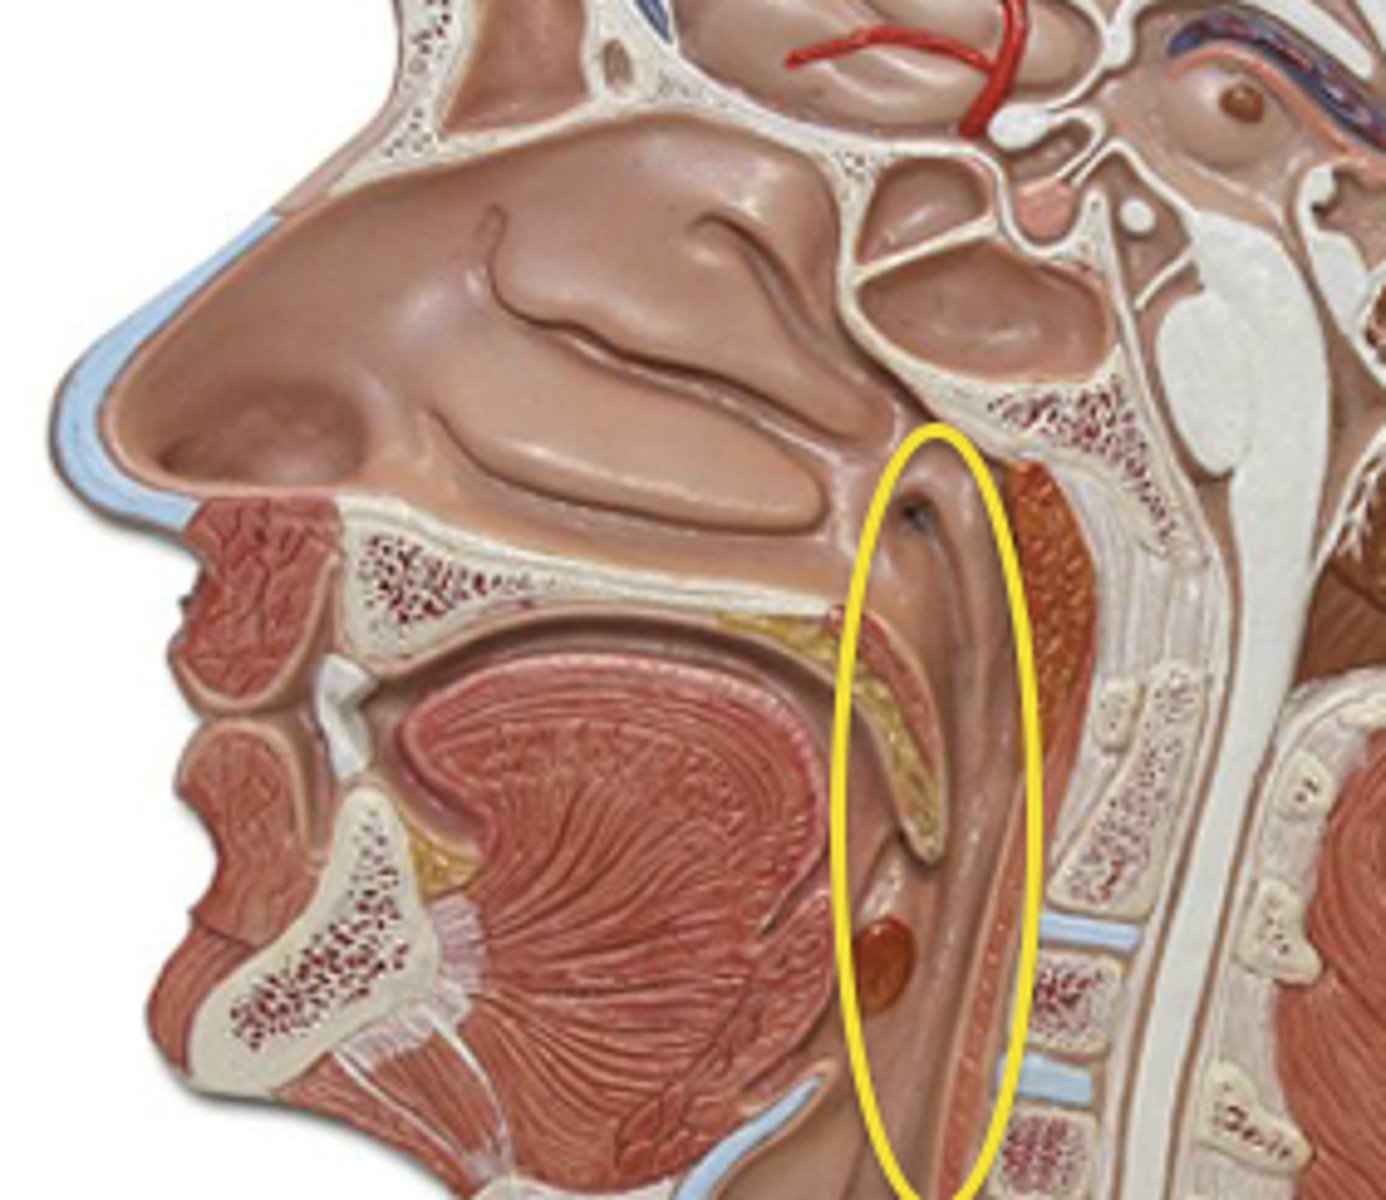

Middle Constrictor Figure

Middle Constrictor Description

Somewhat fan shaped

Origin - hyoid bone

Course - fan out posteriorly and medially

Insertion - midline raphe

Action - reduce diameter of pharynx